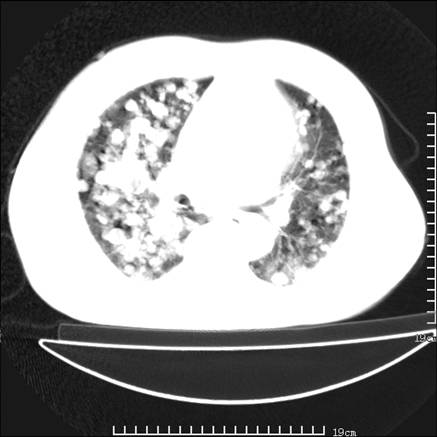

张男,75岁,干咳半年余,小便不利二年,b超检查前列腺增大,未见明显肿块;前列腺癌血生化检查多项指标明显增高。

双肺内多发转移瘤,纵膈淋巴结转移。来源前列腺?建议盆腔mri进一步检查。

双肺转移满了。

两肺广泛转移瘤。